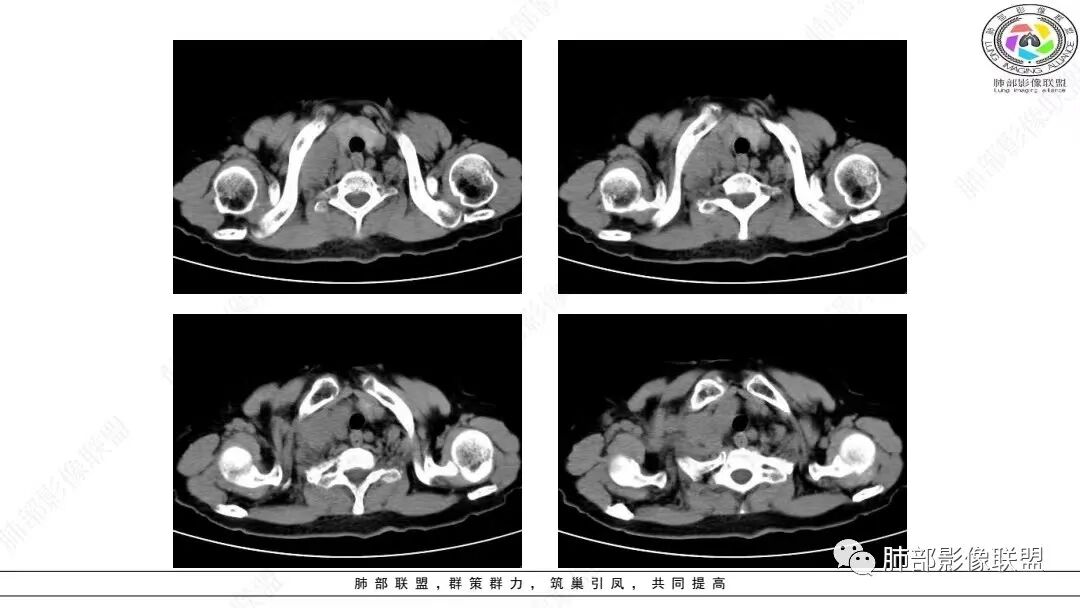

1.临床特点:老年女性,反复上腹部疼痛半年,加重10余天,入院半年前开始出现反复上腹部闷痛,较轻微,偶有嗳气、憋气感,与进食无关,未治疗,10余天上述症状再发,部位性质同前,感全身酸痛,以腹痛待查入院。实验室检查未见明显异常。

2.影像学特点:右肺上叶前段胸膜下不规则较大团块影,边界清楚欠光整,浅分叶,肺血管支气管出入,边缘膨隆胸膜凹陷具有一定张力,未见典型粗短毛刺,部分围以边界清楚的磨玻璃影,灶周小叶间隔增厚。块影密度不均,渐进性强化,可见砂砾样钙化,未见明显液化坏死或空洞。增强后病灶显示渐进性强化。MIP显示病灶内肺动脉穿行、并部分肺动脉受侵变细。纵隔及右锁骨上(胸廓入口)见肿大淋巴结。两肺可见多发大小不一的结节影,边界清楚,随机分布。

胸椎体溶骨性吸收破坏,突破骨皮质。腹部扫描未见肿块影。